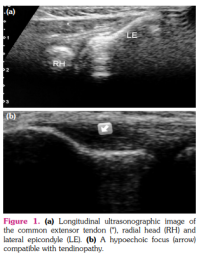

The US-guided injection technique was performed with the elbow bent to 90° and the patients were placed for injection in a seated position facing the physician. The US probe was positioned perpendicular to the common tendon origin to guide all the injections longitudinally. Ultrasound revealed hypoechoic areas and/or loss of normal fibrillar pattern characteristic of tendinopathy in the common extensor tendon. A single skin portal was made immediately distal and anterior to the lateral epicondyle into the common extensor tendon with a 22-gauge needle. The physician was able to follow the route of the needle and PRP was distributed to the pathologic areas of the common extensor tendon identified with US (Figure 1). The US-guided injections were performed using a MyLab60 model US device (Esaote S.p.A., Genova, Italy) with a high resolution and a 7- to 12-MHz linear probe.